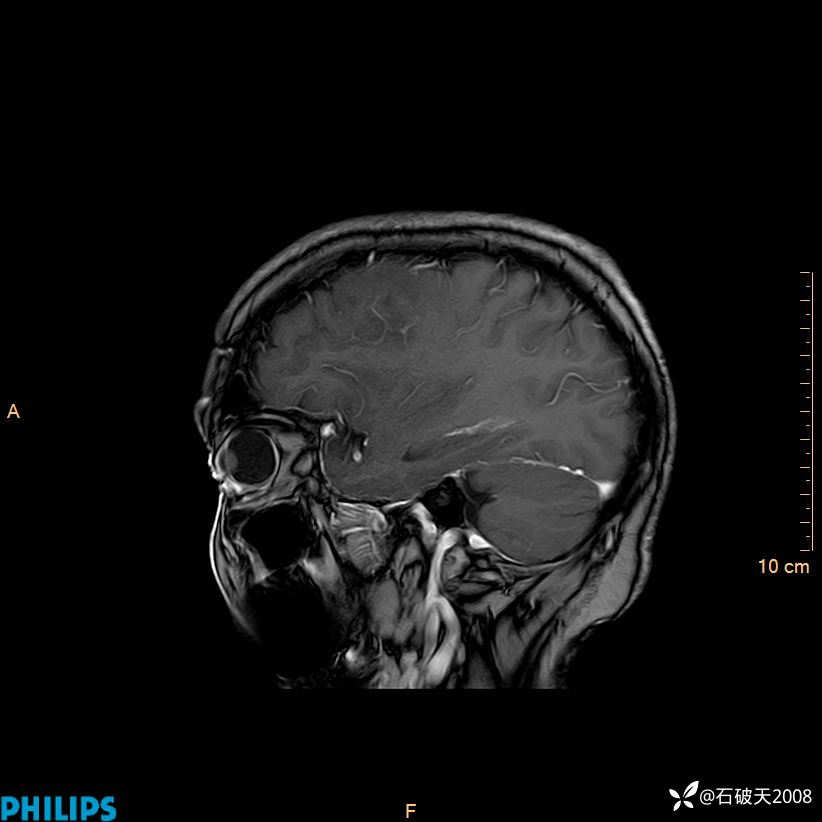

增强矢状位